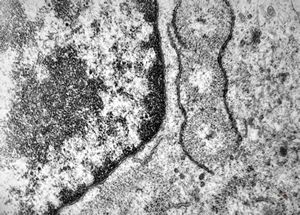

M,41y. | hairy cell leukemia - spleen - ribosome-lamella complex in tricholeukocyte